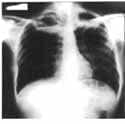

Se encontró estertores y roncus en ambos campos pulmonares, leucocitos de 10.800 /mm3, neutrófilos 91%, la radiografía de tórax (Figura 1), mostró imágenes radio lúcidas circulares con niveles hidroaéreos en ambos ápices pulmonares. Se hace diagnóstico de abscesos pulmonares apicales.

Figura 1.